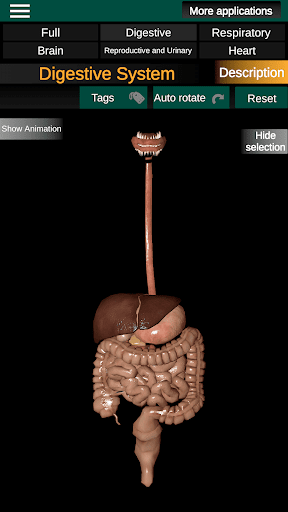

Internal Organs in 3D Anatomy لـ Vodafone Smart N9 Lite

(الأجهزة الداخلية في)

Internal Organs 3D Anatomy 3.4

يمكنك هنا تنزيل ملف حزمة تطبيق أندرويد "Internal Organs 3D Anatomy" الخاصة بجهازVodafone Smart N9 Lite مجانًا، نسخة ملف حزمة تطبيق أندرويد - 3.4 للتحميل على Vodafone Smart N9 Lite اضغط ببساطة على هذا الزر. إنه سهل وآمن. نحن نقدم فقط ملفات حزمة تطبيق أندرويد الأصلية. إذا انتهكت أية مواد موجودة في الموقع حقوقك قم بإبلاغنا من خلال